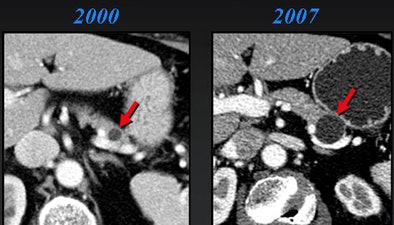

Worrisome features for malignancy are solid tissue within the cyst, obstruction of the main pancreatic duct ≥ 1 cm or the common bile duct, regional lymphadenopathy, or interval enlargement of a lesion, Jeffrey said.

"The presence of solid tissue within cystic lesions in addition to regional lymphadenopathy and interval enlargement are all very significant features suggesting malignancy," Jeffrey said.

Nineteen of the 156 patients had surgery, while only three cases were malignant, Jeffrey said. Most important, all malignancies had solid tissue within the lesion at CT. Interval growth was also a predictor. Lesions grew in seven cases, including two of the three malignancies, Jeffrey said of the study (Abdominal Imaging, January-February 2007, Vol. 32:1, pp. 119-125).

"The take-home message here is that those that have solid internal tissue or enlarge over time have potential for malignancy," he said. "Interval growth was seen in seven cases, two of which were malignant, so obviously benign lesions can also grow over time."